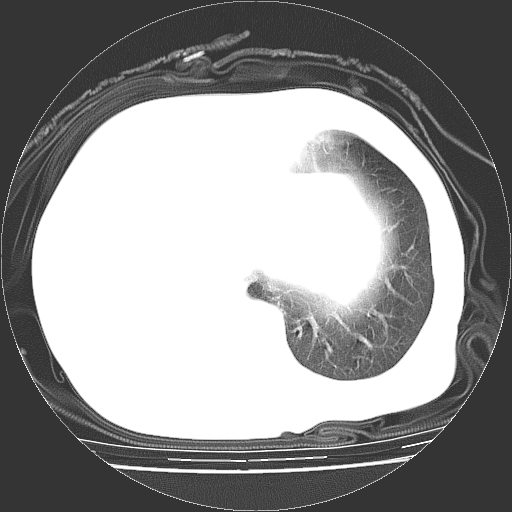

标题: CT23991:女,72岁,咳嗽、憋气一周。 [打印本页]

女,72岁,咳嗽、憋气一周,十年前曾患肺结核及胸膜结核。

右侧毁损肺,右侧纵隔疝

右侧毁损肺,右侧纵隔疝,左肺代偿!

1.右侧损毁肺伴胸膜钙化,2.左肺小结节灶,良性可能大,注意复查。3.肝脏左叶囊肿。4.先天性一侧肺不发育待出外(右侧胸廓无明显塌陷)。对比原片应该非常有帮助。